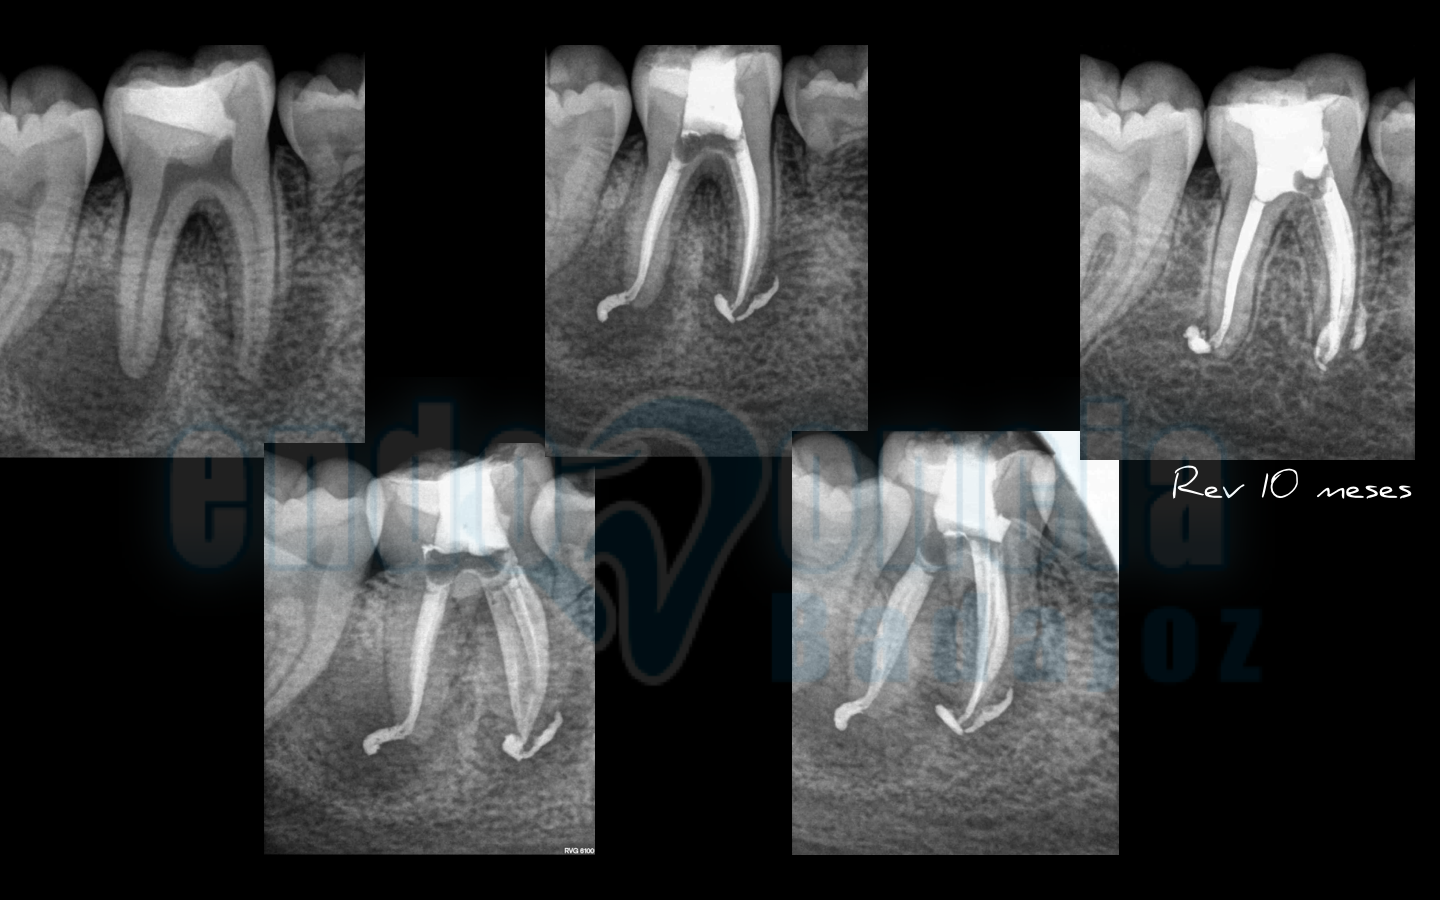

Caso 4:

Premolar inferior, con una periodontitis Apical Asintomática, en el que hacemos un control a los dos años, y vemos una perfecta curación. A los 2 meses tuve un flare-ups.